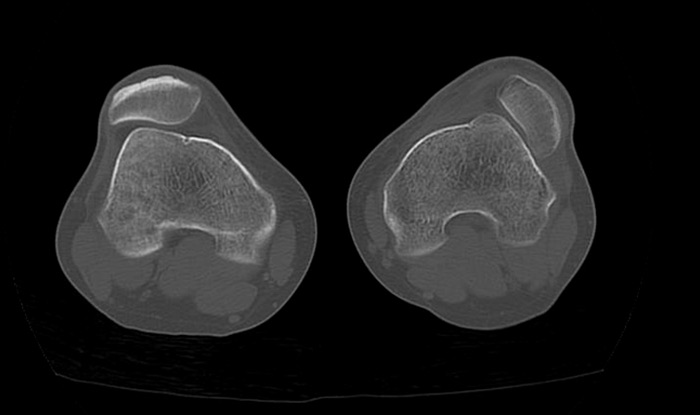

Pre-operative CT-scan

Pre op CT-scan

Pre-operative measurements

• HKA = 180°

• TT-TG = 24 mm

• Femoral neck anteversion (FNA) = 27.5°

• Dejour type C trochlear dysplasia